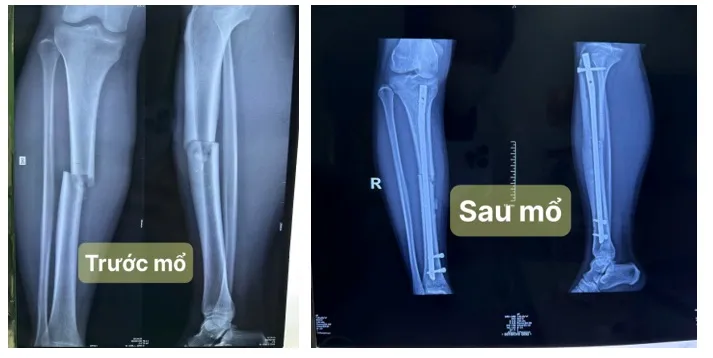

70bgaycangchan1.jpg

Một trường hợp gãy kín xương ống đồng tại Bệnh viện Nhân dân 115

Theo BS Lê Minh Đức, đối với trường hợp gãy xương kín, người bệnh được áp dụng kỹ thuật phẫu thuật can thiệp tối thiểu. Thay vì mổ rộng, các bác sĩ chỉ cần một đường rạch nhỏ dài khoảng 4-5 cm tại gối để đưa một đinh nội tủy vào xương cẳng chân. Hệ thống chụp X-quang tại chỗ (C-arm) hỗ trợ các bác sĩ đảm bảo độ chính xác trong quá trình phẫu thuật. Đặc biệt, việc sử dụng vít chốt ngang giúp giữ cho đinh nội tủy không bị xoay, từ đó giúp quá trình hồi phục diễn ra thuận lợi.